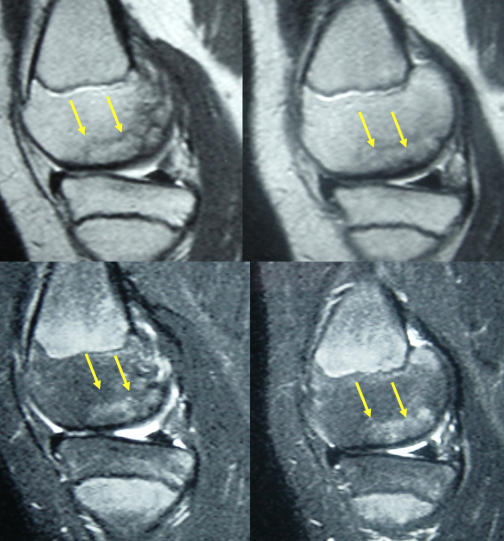

Ergenlik öncesinde saptanan ve altındaki canlı kemik yatağından ayrılmamış olan osteokondritis dissekans, çocukların yarısından fazlasında ameliyatsız iyileşebilir. Bunun için sportif aktivite kısıtlanır ve 6 aylık aralarla MRG takibi yapılır. Üzerindeki kıkırdağın bütünlüğü bozulmamış ve MR’larda ayrılma bulgusu yoksa, ölü kemik vücut tarafından onarılarak 2 yıl içinde iyileşme sağlanabilir (Resim 3). Bu takip için kaliteli bir MR görüntülemesi şarttır. MRG’lerde ayrılma bulgusu saptanan çocuklarda cerrahi tedavi gerekli olur. Her iki dizde osteokondritis varsa, seyirleri aynı olmayabilir. Bir taraf iyileşirken diğer taraf ayrılıp ameliyat gerektirebilir.

Resim 3 a,b: Ergenlik öncesi osteokondritis dissekans saptanan bir hastada ameliyatsız iyileşme. a: İlk başvuru anındaki MR görüntüleri; b: İki yıl sonra kıkırdak ayrılması olmadan iyileşme tamamlanmış.